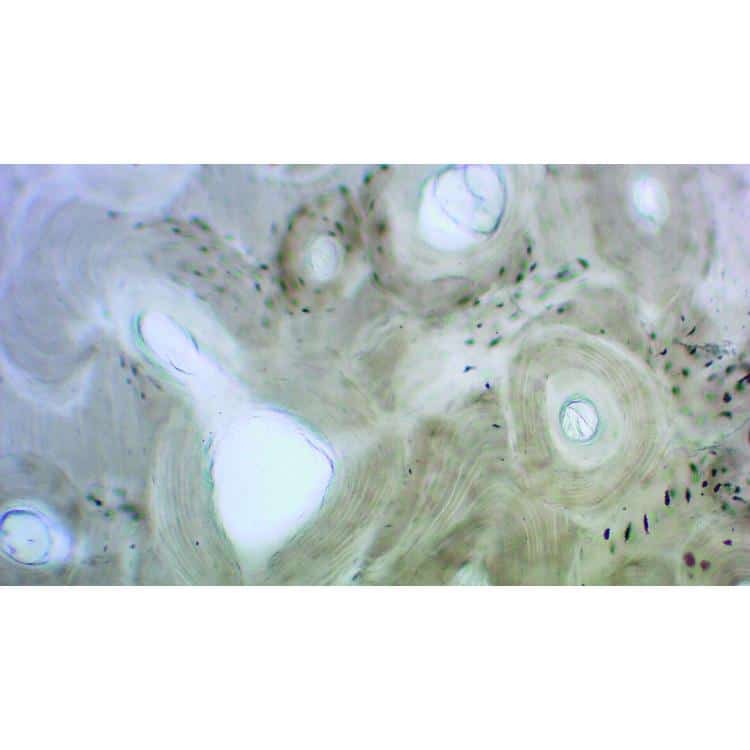

Mikroskopiske præparater: Histologi af hvirveldyr – Menneskelig tør kompakt knogle

Menneskelig tør kompakt knogle